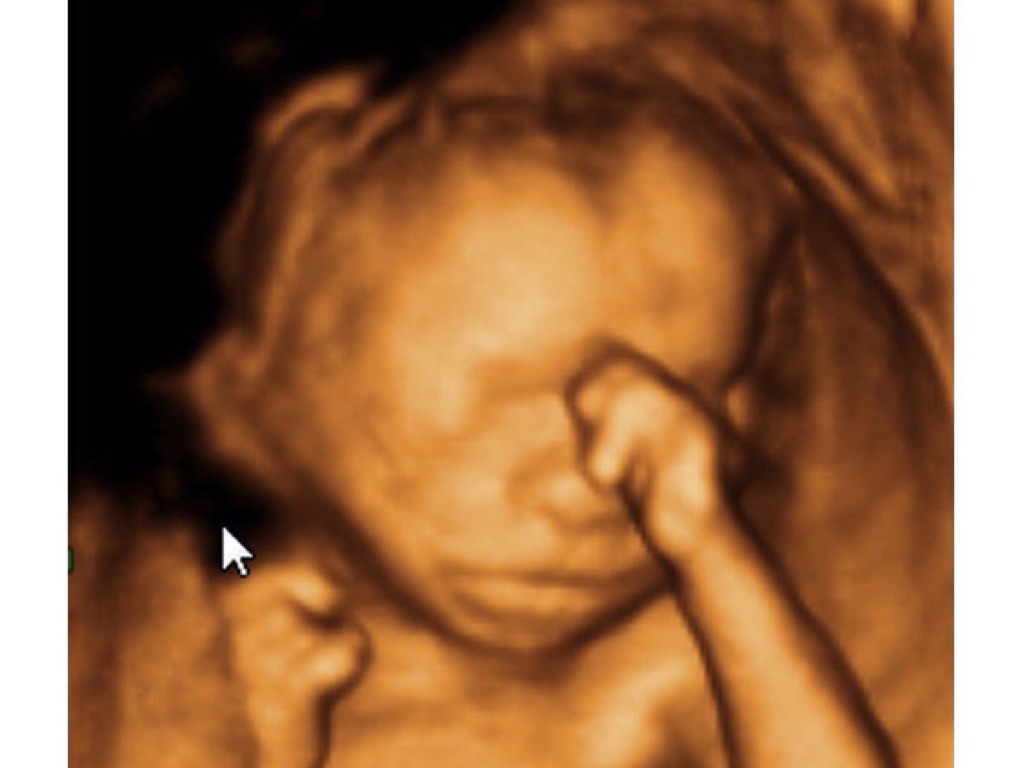

MEDICAL TECHNOLOGY

Technology plays an increasingly important role in modern medicine. Today, HI-TECH IMAGING allows doctors to view internal body structures in amazing detail, while, SURGERY relies heavily on technologies such as lasers, robots, and computers. ARTIFICIAL DEVICES are commonly used either to replace diseased body parts completely, or to provide assistance to failing organs.

3-D MRI SCAN

Magnetic Resonance Imaging

MRI (magnetic resonance imaging) is an advanced imaging technique. The body part to be examined is placed inside a powerful magnet, and harmless radio waves are released towards it. A computer then builds an image by analysing the pattern of radio waves returned from the part. MRI is often used to examine the brain and other soft tissues.

INDEED

Modern imaging methods can provide detailed pictures of body parts, whether by injecting dyes that highlight specific structures on X-ray viewing, or by using methods that provide cross-sectional or 3-D scans. Some techniques provide information on body activity, not just structure. For example, special forms of ultrasound (high-frequency sound) can be used to monitor the flow of blood within blood vessels. The internal structures of the body can also be examined directly by means of fibreoptic endoscopes (viewing tubes).